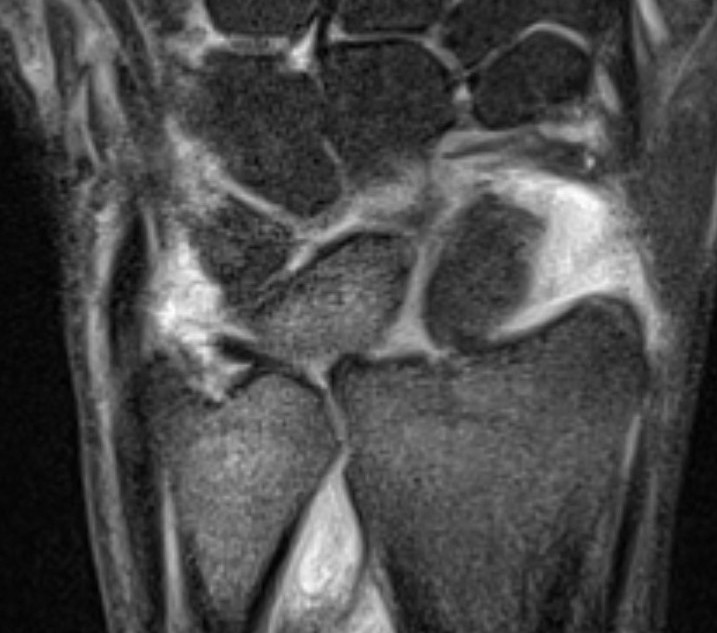

Ulno-carpal abutment

Ulnocarpal abutment and lunate chondromalacia

Ulna positive with ulnocarpal osteoarthritis

Class 2 Degenerative TFCC tears

Central TFCC tear with ulna positive variance an ulnocarpal abutment on MRI